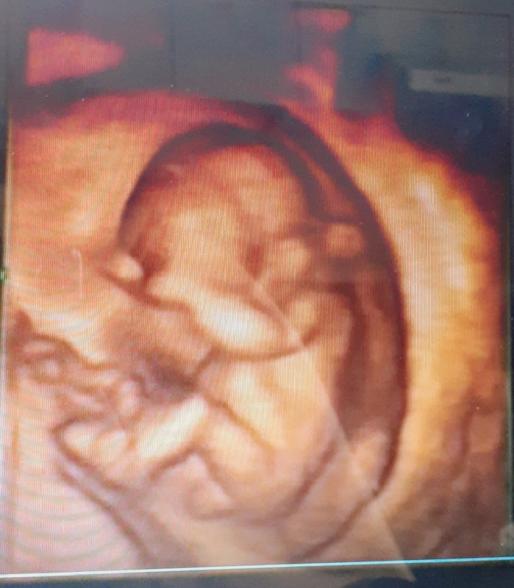

先日12週4日の時に、妊婦健診に行ってきました。

性別が分かると嬉しいのですが、4Dエコー写真から、性別は分かりますでしょうか?

また、まだこの時期では、分からないでしょうか?